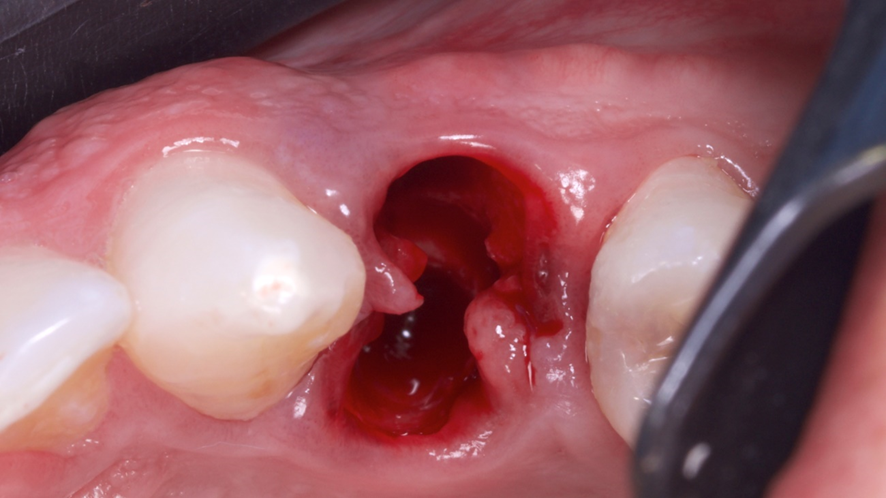

Visto todos os planejamentos realizados, buscou-se então dar ínicio ao procedimento cirúrgico. A exodontia foi realizada de forma minimamente invasiva, utilizado periótomos (Supremo) fazendo movimentos de lateralidade, buscando descolar as fibras periodontais do dente, visando assim conservar ao máximo os tecidos gengivais adjacentes após essa etapa, até sua avulsão.

Após a exodontia foi posicionado o guia cirúrgico impresso e iniciou-se o protocolo de fresagem do kit cirúrgico Implaguide da Implacil De Bortoli: fresa lança 2,0, seguida pela fresa 3,5×13, buscando subfresagem para maior estabilidade primária. O implante dentário instalado foi o Maestro de 4x13mm (Implacil De Bortoli). Foi realizado em seguida a instalação do pilar Ideale 4,5 x 4 x 2,5 mm e a coifa parafusada do pilar Ideale 4,5x4mm.

O GAP vestibular foi preenchido com enxerto ósseo heterógeno com matriz colágeno Extra Graft (Implacil De Bortoli), o qual foi colocado e compactado.